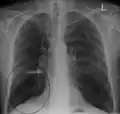

A chest X-ray is not useful to establish a diagnosis of COPD, but it is of use in either excluding other conditions or including comorbidities such as pulmonary fibrosis and bronchiectasis. Characteristic signs of COPD on X-ray include hyperinflation (shown by a flattened diaphragm and an increased retrosternal air space) and lung hyperlucency.[5] A saber-sheath trachea may also be shown that is indicative of COPD.[111]

- Chest X-ray demonstrating severe COPD, displaying small heart size in comparison to the lungs